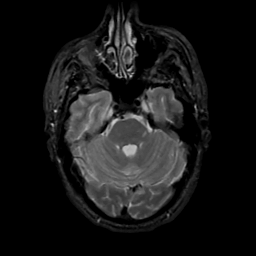

MR Study #15, June 9, 1991 -- Slice #14

[Home][Help][Clinical][Tour 1][Tour 2] Slice 14